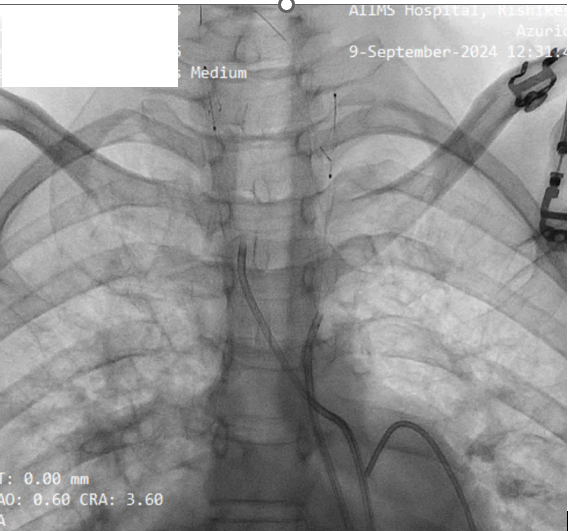

Given prohibitive surgical risk, high-risk BMV was attempted. Bilateral carotid angiography was performed and SpiderFx embolic protection devices (Medtronic, USA) deployed. Under TEE guidance, transseptal puncture was done, and an Inoue balloon (Toray, Japan) was advanced across the mitral valve. Sequential dilatations reduced the mean gradient with no embolic debris in filters. The patient improved hemodynamically and was discharged in stable condition.

The patient was deemed prohibitive risk for surgical mitral valve replacement with clot extraction, so a high-risk percutaneous approach was planned. Bilateral carotid angiography was performed, and 5 mm SpiderFx embolic protection devices (Medtronic, Minneapolis, MN, USA) were deployed to minimize embolic risk. Transseptal puncture was guided by transesophageal echocardiography because of a thin interatrial septum. An Inoue balloon catheter (Toray, Tokyo, Japan) was advanced across the mitral valve, and sequential graded dilatations were performed under fluoroscopy. Mean transmitral gradient fell markedly, with corresponding fall in pulmonary artery pressure. The embolic filters were retrieved without visible debris. The procedure was uneventful, with no neurological events. The patient was extubated on table, remained hemodynamically stable, and reported significant symptomatic improvement. She was discharged in NYHA class II and, at follow-up, was able to resume routine activities with sustained benefit.